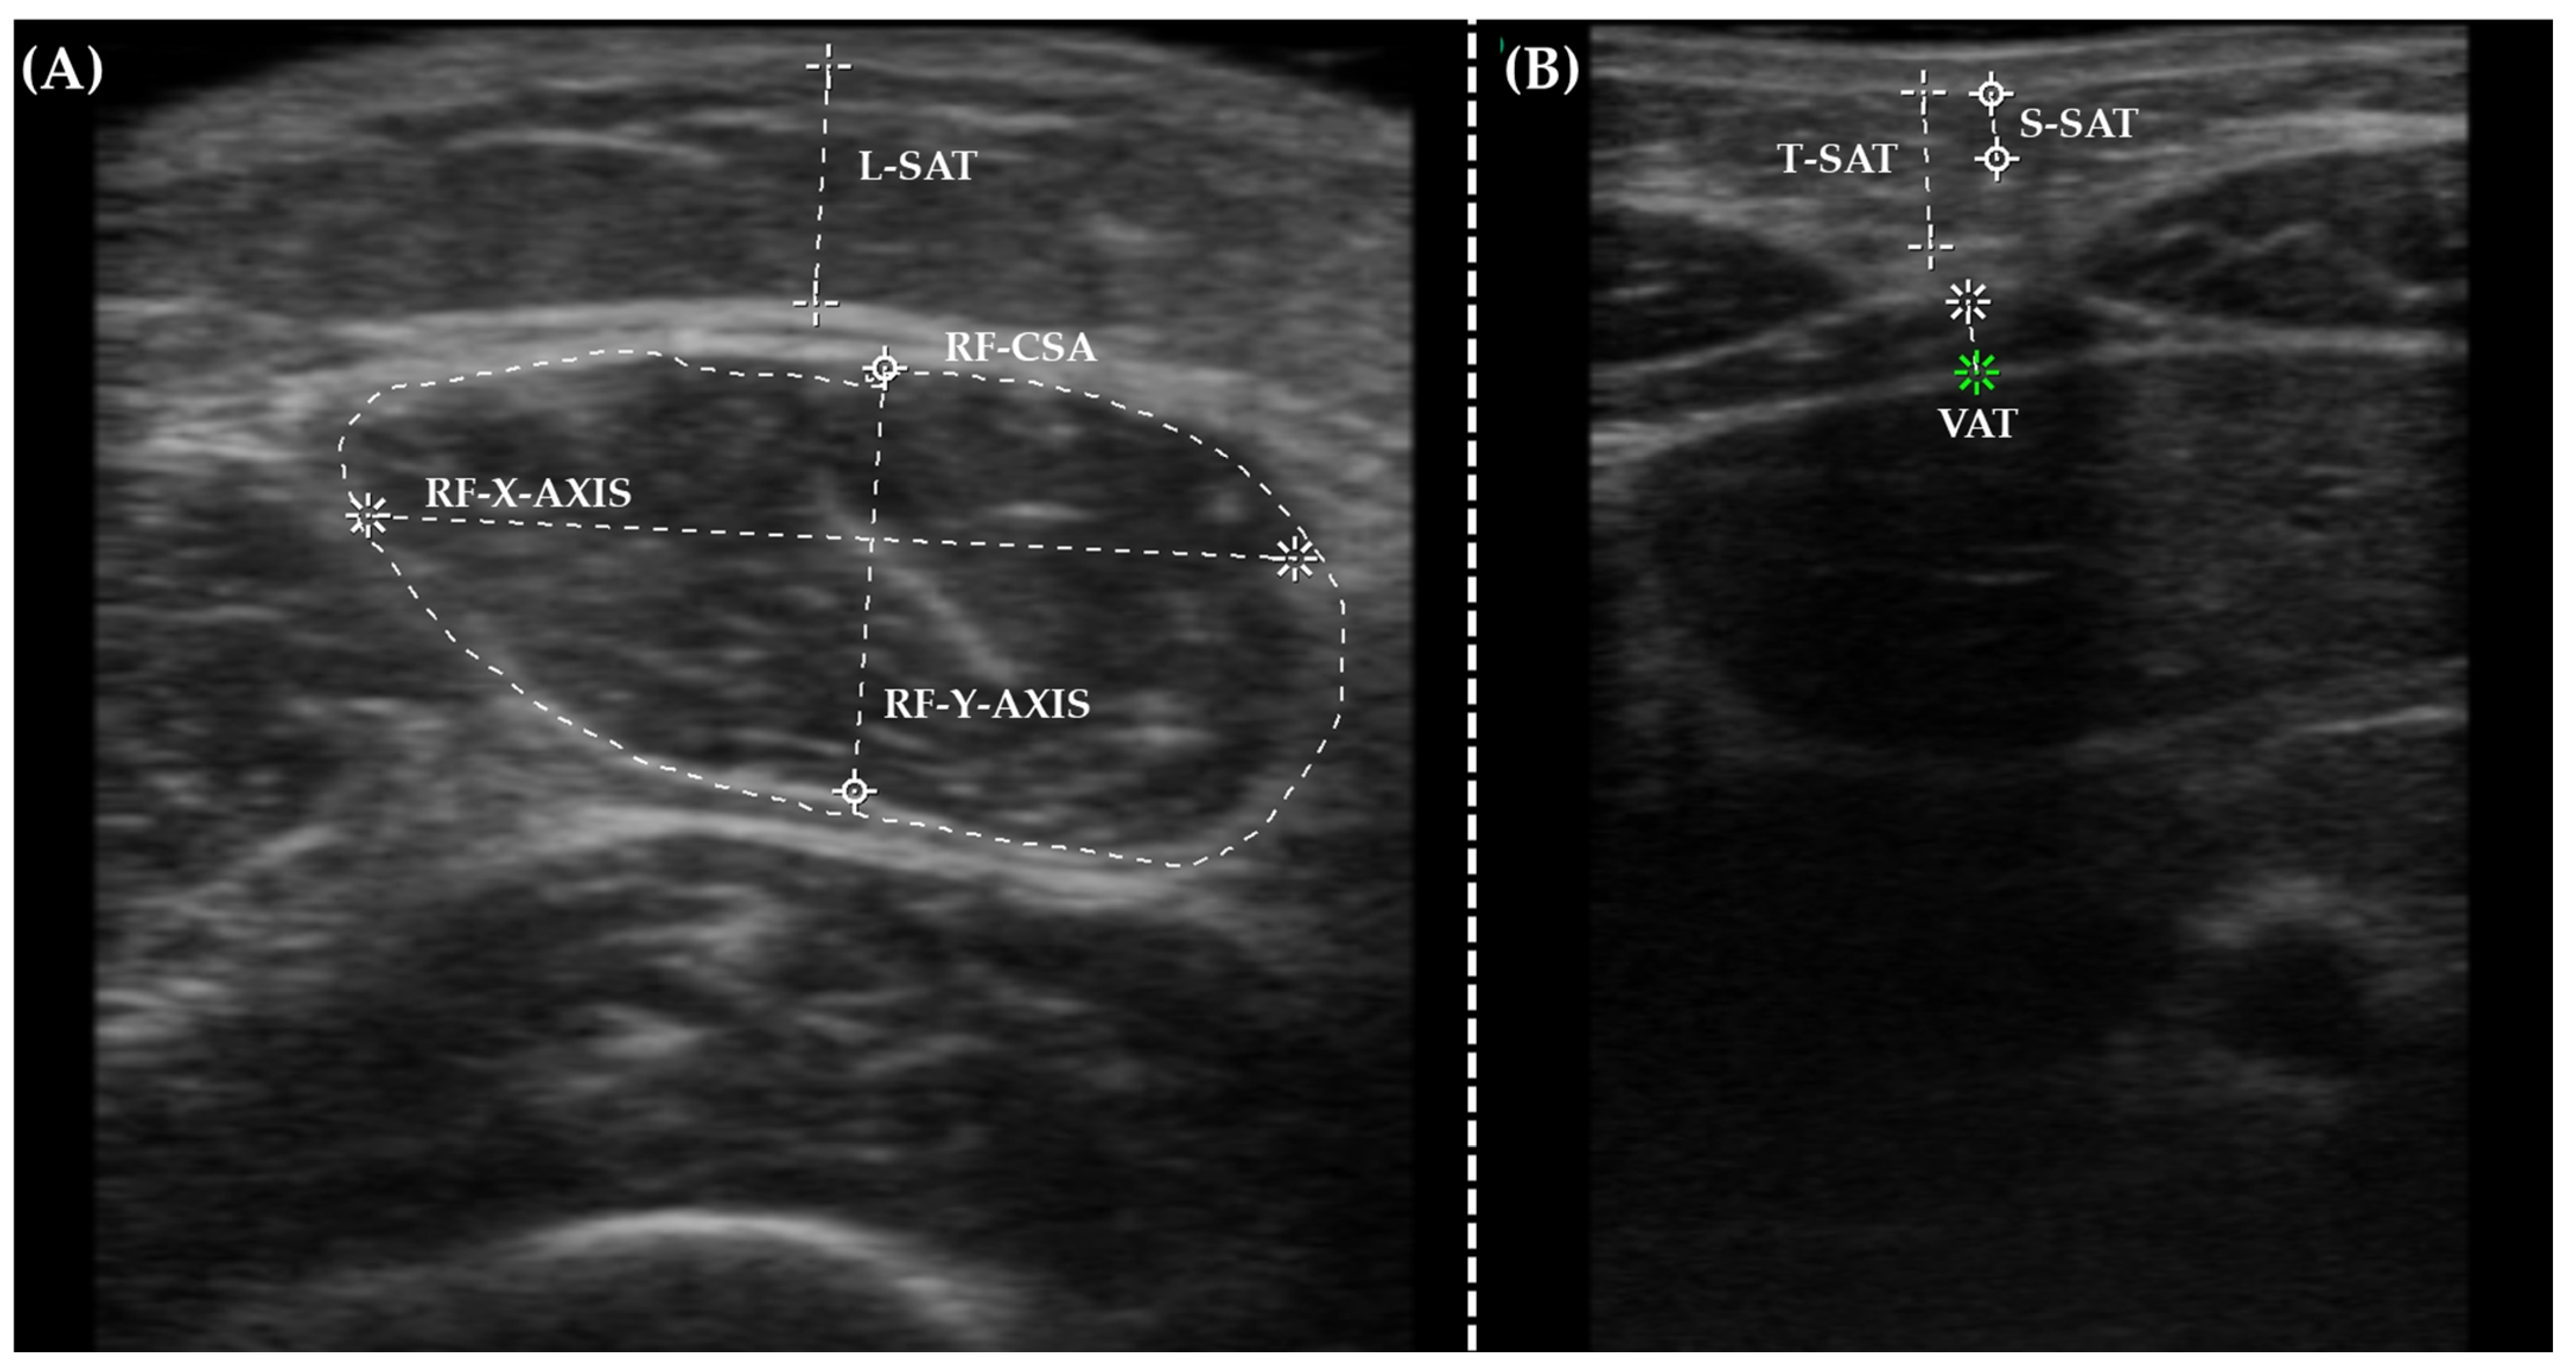

2.5. Nutritional Ultrasound®

| Nutritional Ultrasound® | |||||

| RF-CSA (cm2) | 3.2 (1.5) | 1.4–4.0 | 3.7 (1.3) | 3–4.4 | 0.284 |

| RF-X-axis (cm) | 3.4 (1.6) | 2.9–4.0 | 3.2 (1.1) | 2.9–3.4 | 0.750 |

| RF-Y-axis (cm) | 1.2 (0.55) | 0.8–1.7 | 1.5 (0.5) | 1.3–1.7 | 0.413 |

| L-SAT (cm) | 0.4 (0.26) | 0.1–1.1 | 0.7 (0.27) | 0.4–1.3 | 0.270 |

| T-SAT (cm) | 0.5 (0.3) | 0.2–1.1 | 0.9 (0.3) | 0.7–1.3 | <0.05 |

| S-SAT (cm) | 0.3 (0.2) | 0.1–0.8 | 0.4 (0.2) | 0.3–0.6 | 0.074 |

| VAT (cm) | 0.3 (0.1) | 0.1–0.5 | 0.4 (0.1) | 0.2–0.6 | 0.154 |